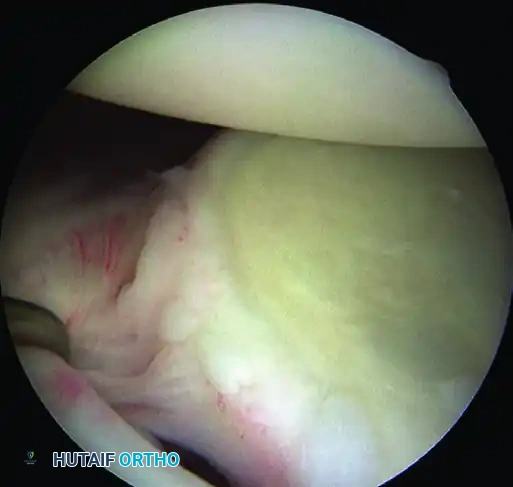

1. Capsulolabral Mobilization and Glenoid Preparation

The most common cause of failure in Bankart repair is inadequate mobilization of the capsulolabral complex.

While visualizing from the anterosuperior portal, use an arthroscopic elevator or radiofrequency wand to meticulously free the capsule down to the 6-o’clock position. You must release the tissue until the underlying red muscle belly of the subscapularis is clearly visible. This complete release is mandatory to allow the inferior capsule to be shifted superiorly without tension.

💡 CLINICAL PEARL: The Biological Bed

Soft tissue healing requires a robust vascular response. Use an arthroscopic rasp or motorized burr to abrade the anterior glenoid neck down to bleeding cancellous bone. Do not over-resect the bone, as preserving the cortical edge is necessary for secure anchor purchase.

A, Abrasion of glenoid neck and capsular release to allow advancement of capsulolabral complex superiorly and laterally to restore anatomy and physiological tension.